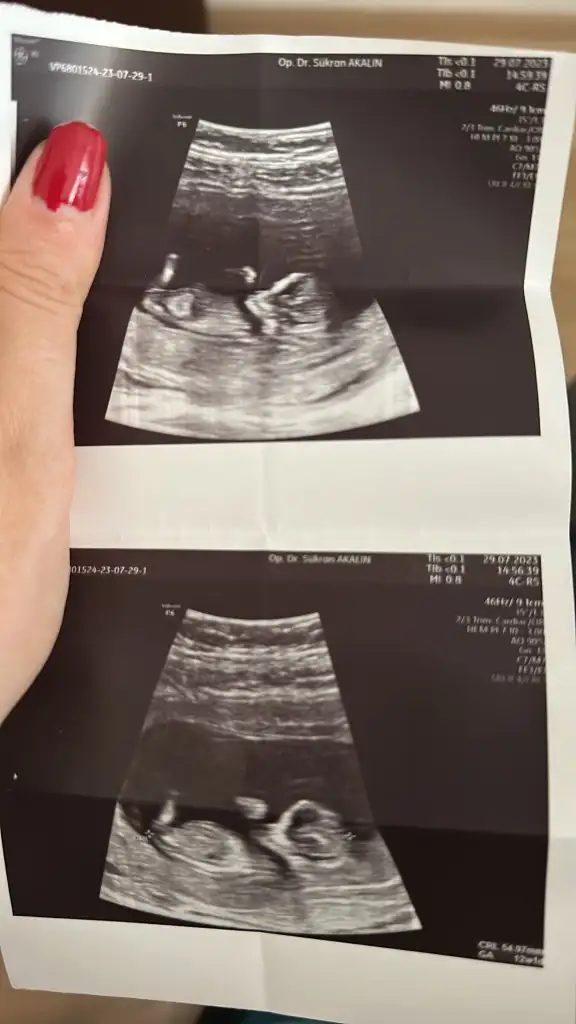

Ölçüm vs doktor daha iyi bilir canım ama diğer ultrason resimlerinden hiç farkı yok bebişin